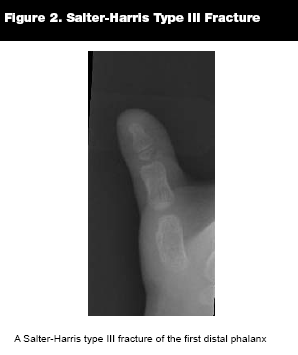

Type III. Salter-Harris III fractures are intra-articular fractures of the epiphysis that extend across the physis. (See Figure 2.) They account for approximately 10% of physeal fractures.11 The prognosis is generally good, but more guarded than with type I or II fractures and is related to the preservation of the blood supply.2 Since type III injuries occur predominantly in older adolescents, the physis has less remaining growth potential, and therefore seldom results in significant shortening. The subspecialist's treatment goal is to anatomically realign the joint surface.5 Orthopedic consultation in the ED is often required.